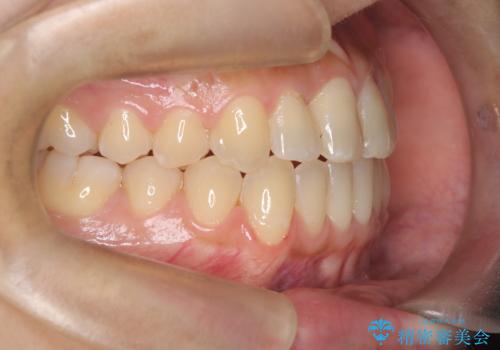

- 患者様は左上の八重歯を気にされて来院されました。八重歯による歯列の乱れだけでなく、翼状捻転(歯がねじれるように生えている状態)も見られました。目立たない矯正を希望されていたため、**インビザライン(マウスピース矯正)**を選択し、左上の小臼歯を抜歯してスペースを作りながら歯を並べる治療計画を立てました。しかし、治療の途中で翼状捻転の改善が十分に進まなかったため、患者様の希望も踏まえ、上顎のみワイヤー矯正に変更することとなりました。

治療開始時はインビザラインを使用し、全体の歯並びを整えながら抜歯スペースを活用して歯を後方へ移動させました。しかし、左上の八重歯のねじれが強く、マウスピースのみでは十分にコントロールできないことが判明。そこで、より細かく歯を動かすために上顎のみワイヤー矯正へ切り替えました。ワイヤー矯正によって翼状捻転も改善し、最終的にバランスの取れた歯並びと噛み合わせを実現。患者様からは「長い治療だったけれど、しっかり整って満足」と嬉しいお言葉をいただきました。